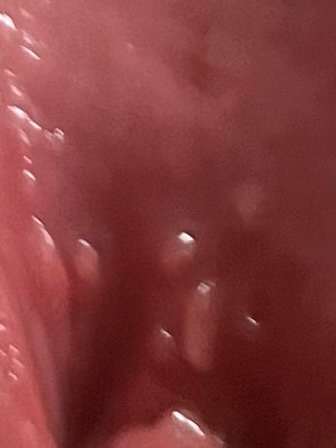

생리 중에 성관계를 가진 후 생식기에 가려움증, 붉어짐, 부음, 그리고 오돌토돌한 것이 생겼다면 여러 가능성을 고려해볼 수 있습니다. 성병의 가능성도 있지만, 그 외에도 질염, 피부 자극, 알레르기 반응, 혹은 질 내부의 PH 불균형으로 인한 문제일 수 있습니다. 오돌토돌한 부분이 생긴 것은 헤르페스와 같은 특정 성병의 증상일 수도 있으나, 반드시 그렇다고 단정 지을 수는 없습니다. 증상이 지속되거나 걱정이 된다면 성병을 포함하여 다양한 질환을 진단할 수 있는 산부인과와 상담하는 것이 좋습니다.

단순한 세균 감염일 수 있고 관계도중 마찰에 의해 점막이 손상되며 나타날수 있습니다.

보다 명확한 평가 위해 부인과 내원하시길 바라며 적절한 항생제 및 약물 처방 받기 권유드립니다.